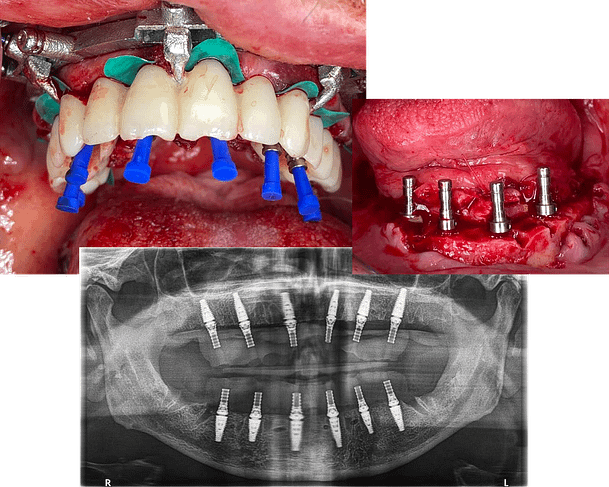

It goes in-depth on the surgery process and what to expect with all the minute details of a live patient course. You’ll also see case examples for different scenarios you might encounter and how to overcome any complications as well.

Before

After